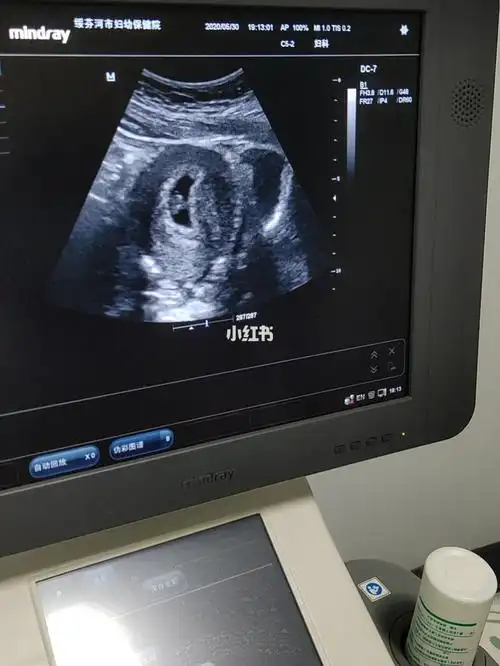

停经59天才看到胎芽胎心,没人比我更晚吧!

有胎心胎芽啦,可以建档啦,宝宝很健康!开心,希望一路顺利